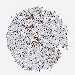

CANCER BREAST CANCER Show tissue menu

BRCA TCGA BRCA VALIDATION PROTEIN EXPRESSION

ANTIBODIES

AND

VALIDATION